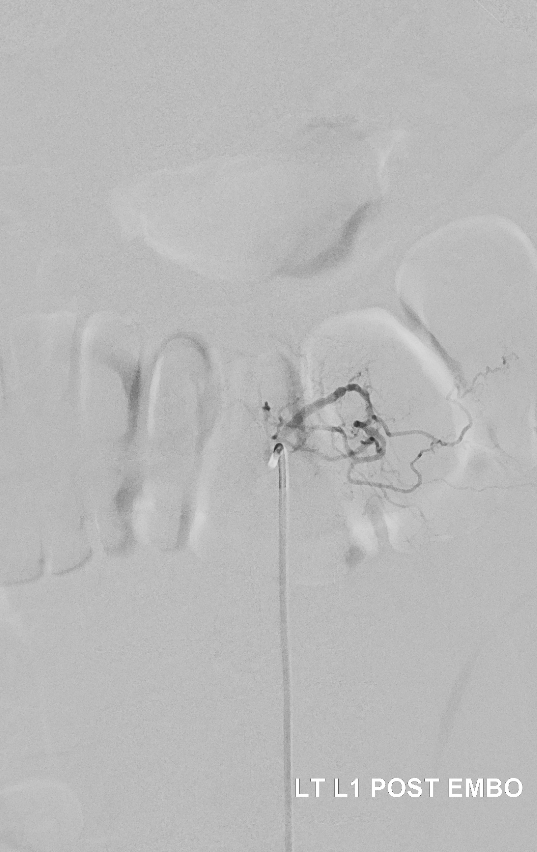

Post. It is important to control from other levels (left T12, left L2, and right L1) — not shown.

Key image here — injection of Adamkiewicz now shows return of the prodigal veins to the venous phase of the cord. Image on left also shows the now liberated basket.